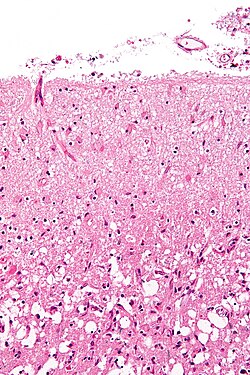

Ishemijski moždani udar nastaje zbog gubitka opskrbe krvlju dijela mozga što pokreće ishemijsku kaskadu[29]. Moždano tkivo prestaje funkcionirati ako je uskraćen dotok kisika dulje od 60 do 90 sekundi, a nakon otprilike tri sata dolazi do nepovratnih ozljeda koje dovode do smrti tkiva, tj. do moždanog udara. (To je razlog zašto se fibrinolitici, kao što je alteplaza, daju samo unutar tri sata od nastanka moždanog udara.) Ateroskleroza može poremetiti dotok krvi suženjem lumena krvne žile što dovodi do smanjenja protoka krvi i posljedično do stvaranja krvnih ugrušaka u krvnoj žili ili otpuštanjem mnoštva komadića malih embolusa raspadom ateroskelortskih plakova[30]. Embolijski infarkti nastaju kada se embolusi formirani negdje drugdje u tijelu, obično u srcu kao posljedica atrijske fibrilacije ili u karotidnim arterijama, otkinu, uđu u moždanu cirkulaciju, te se smjeste i začepe krvnu žilu. Budući da su sad krvne žile u mozgu začepljene, u mozgu pada razina energije, što rezultira prijelazom na anaerobni metabolizam u području moždanog tkiva zahvaćenog ishemijom. Nažalost, ova vrsta metabolizma proizvodi manje adenozin trifosfata (ATP), ali ispušta i nusproizvod pod nazivnom mliječna kiselina. Mliječna kiselina je iritans koji mi mogao uništiti stanice, jer je kiselina i ometa normalnu acido-baznu ravnotežu u mozgu. Područje ishemije se naziva „ishemijska penumbra“[31].

Zatim, dolazi do smanjenja koncentracije kisika i glukoze u području ishemije, proizvodnja viskoenergetskih fosfatnih spojeva kao što je adenozin trifosfat (ATP) ne uspijeva, što dovodi do propadanja energetski ovisnih procesa (kao što je rad ionskih pumpi) potrebnih za preživljavanje stanice. To dovodi do pokretanja cijelog niza povezanih događaja što kao posljedicu ima oštećenje stanice i njezinu smrt. Glavni uzrok ozljede neurona je oslobađanje stimulacijskog neurotransmitera glutamata. Koncentracija glutamata izvan stanica živčanog sustava obično se održava niskom uz pomoć tzv. apsorpcije nosača, koji se napaja iz koncentracijskog gradijenta iona (uglavnom Na+) preko stanične membrane. Međutim, moždani udar prekida dotok kisika i glukoze koji pokreću te ionske pumpe potrebne za održavanje tih gradijenata. Kako rezultat nastaje pad ionskog gradijenta i glutamatni tranporteri preokreću svoj smjer, otpuštajući glutamat u izvanstanični prostor. Glutamat djeluje na receptore na živčanim stanicama (posebice NMDA receptore), dovodeći do priljeva kalcija koji aktivira enzime koji razgrađuju stanične bjelančevine, lipide i sadržaj jezgre. Priljev kalcija također može dovesti do propasti mitohondrija, što može dalje dovesti do gubitka energije i može potaknuti staničnu smrt putem apoptoze.

Ishemija također potiče nastanak slobodnih radikala kisika i drugih reaktivnih kisikovih spojeva. Oni reagiraju s brojnim staničnim i izvanstaničnim strukturama i oštećuju ih. Posebno je važno oštećenje sluznice ili endotela krvnih žila. U stvari, mnogi neuroprotektivni antioksidansi poput mokraćne kiseline i NXY-059 djeluju na nivou endotela, a ne na moždanom tkivu. Slobodni radikali također mogu izravno pokrenuti elemente kaskade apoptoze pomoću redoks signalizacije.

Ti procesi su isti za bilo koju vrstu ishemijskog tkiva i nazivaju se zajedničkim imenom ishemijskom kaskadom. Međutim, moždano tkivo je posebno ranjivo na ishemiju jer ima malu respiratornu rezervu i potpuno je ovisno o aerobnom metabolizmu, za razliku od većine drugih organa.

Osim štetnih utjecaja na moždane stanice, ishemija i infarkt mogu rezultirati gubitkom i strukturalnog integriteta moždanog tkiva i krvnih žila, dijelom kroz oslobađanje metaloproteinaza, koje su cink i kalcij ovisni enzimi koji razgrađuju kolagen, hijaluronsku kiselinu i druge elemente vezivnog tkiva. Ostale proteaze također pridonose ovom procesu. Gubitak integriteta vaskularnih struktura rezultira slomom zaštitne krvno-moždane barijere i doprinosi moždanom edemu, koji može uzrokovati sekundarnu progresiju moždane ozljede.

Hemoragijski moždani udar

Hemoragijski moždani udar rezultira ozljedom tkiva uslijed kompresije tkiva prilikom širenja jednog ili više hematoma. To može narušiti i ozlijediti tkivo. Osim toga, tlak može dovesti do gubitka krvne opskrbe u zahvaćenom području što rezultira infarktom, a krvi otpuštena prilikom moždanog krvarenja čini se da ima izravno toksično djelovanje na moždano tkivo i krvne žile. Upala doprinosi sekundarnom oštećenju nakon krvarenja[15][32] Inflammation contributes to the secondary brain injury after hemorrhage.[32] .